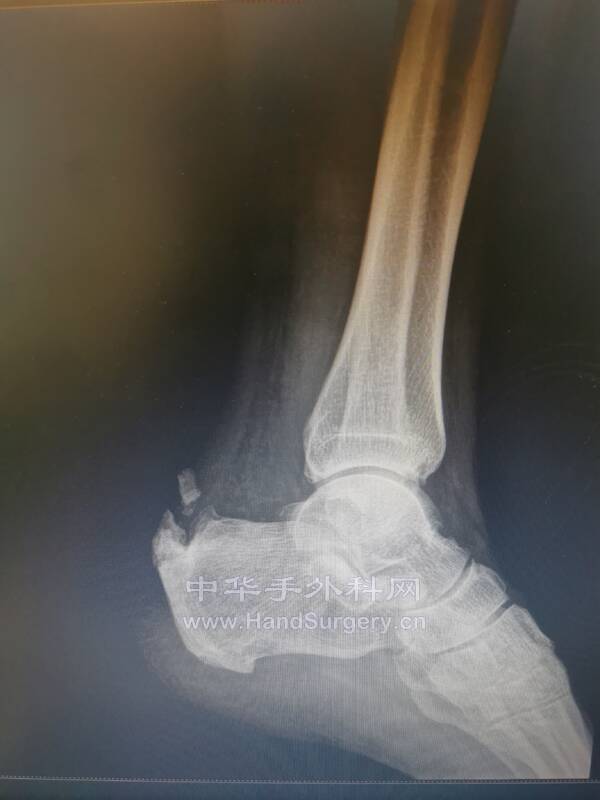

比如这个患者

跟腱止点断裂

手术后,在返回来从新阅读影像学资料

可以更加直观、清晰的读取影像资料的内涵